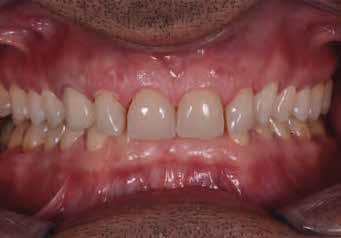

A fogak extrahálása és az alveoláris plasztika teljes narkózis mellett történt meg, így teremtve ideális helyzetet a protetikai ellátáshoz. A műtéti beavatkozás után a páciens az ideglenes fogsorral távozott. Egy héttel később jött kontrollra. Nemcsak látványra változott meg nagymértékben, hanem egyértelműen magabiztosabb és önbizalommal teli volt a fellépése (12. ábra)

Az elsődleges terápiás szakasz kulcsfontosságú volt a teljes rehabilitáció szempontjából. A páciensnek nem csak szép, esztétikus mosolyt kölcsönzött, hanem életminőségének javulását is hozta (13. ábra). A Digital Denture folyamatnak köszönhetően a kezelés ráfordításai is alacsonyak voltak. A fiatal nő messzemenően boldog, magabiztos és motivált a következő lépéshez.

12. ábra: Páciensünk egy héttel fogainak extrahálása és az ideglenes fogsor azonnali behelyezése után. 13. a–d ábrák: Látványos átalakulás: kezelés előtt és után. A páciens maga hangsúlyozta ki életminőségének jelentős javulását.